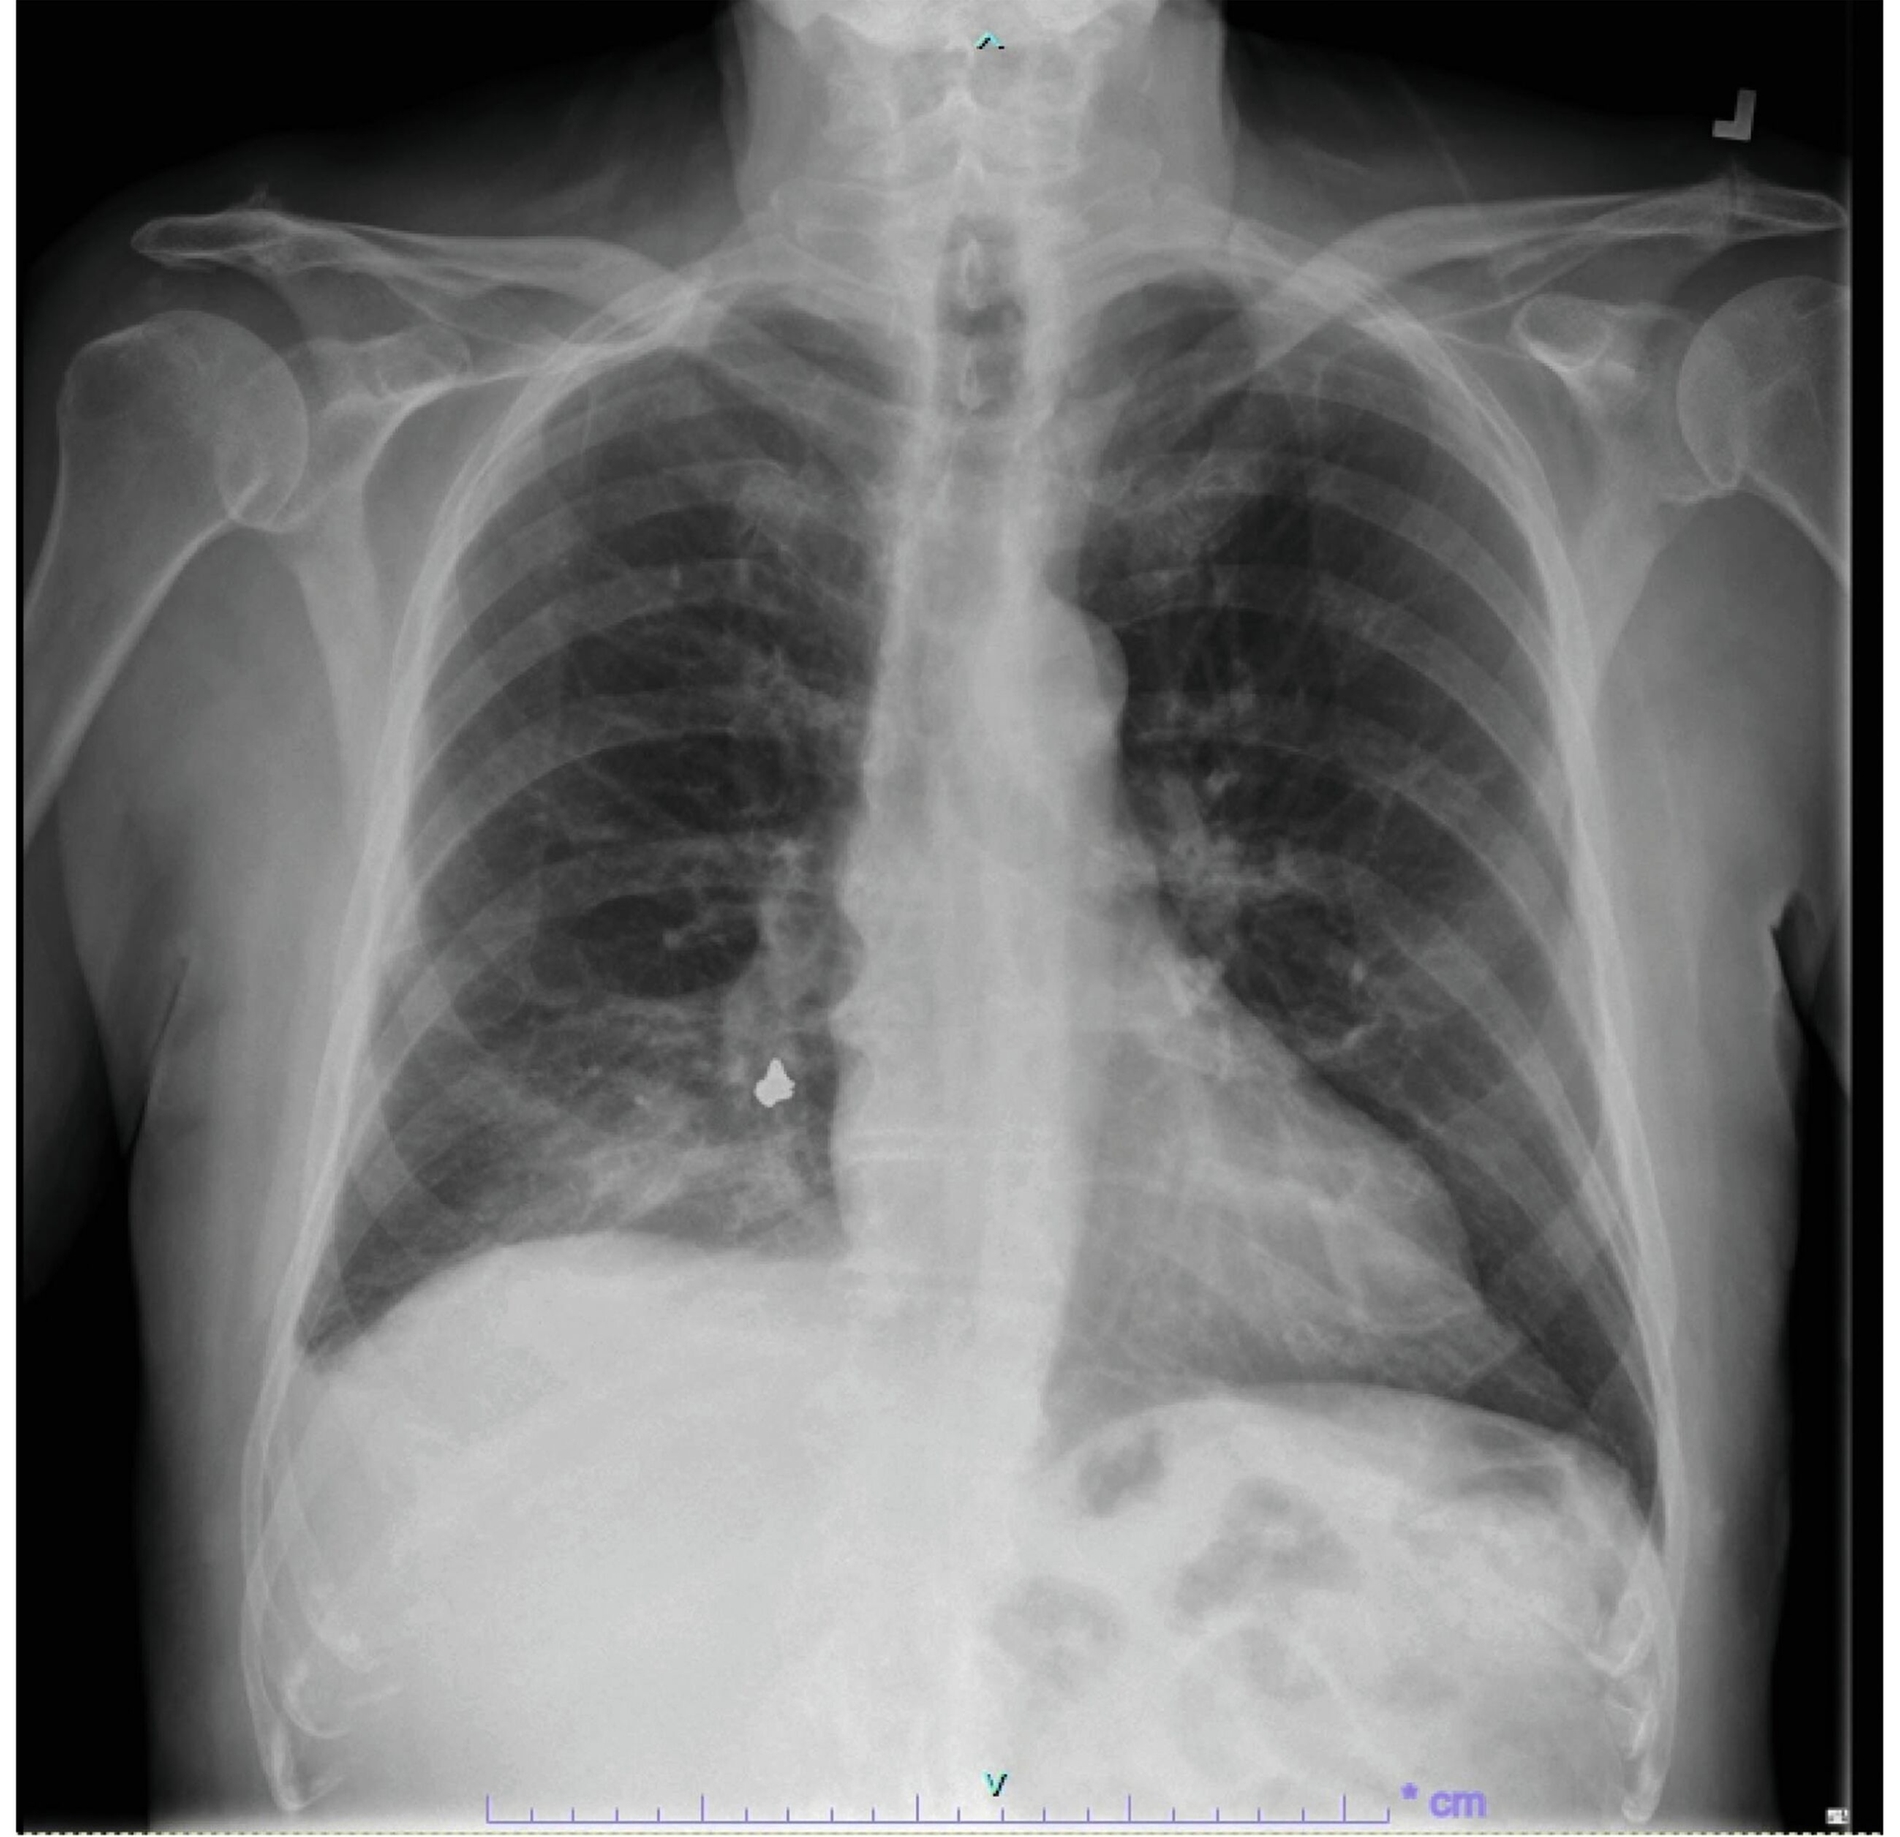

Der 93-jährige Patient stellte sich in der Notaufnahme in reduziertem Allgemeinzustand, Husten und Kurzatmigkeit vor. Seit Symptombeginn vier Tage zuvor hatte sich der Zustand des Patienten trotz Antibiotika-Therapie verschlechtert. In der Röntgenaufnahme des Thorax zeigte sich im infrahilären Bereich eine Verschattung, die den Verdacht auf einen Fremdkörper bestätigte. Zur genaueren Lokalisation wurde ein CT des Brustkorbs angefertigt. Der Fremdkörper wurde im subsegmentalen Bronchus im hinteren, rechten Unterlappen lokalisiert. Des Weiteren zeigte sich eine distale Konsolidierung, die mit einer postobstruktiven Pneumonie vereinbar war. Der Fremdkörper wurde anschließend mittels Bronchoskopie entfernt. Es handelte sich um eine Zahnkrone aus einer Goldlegierung mit umliegendem, purulentem Schleimmaterial. Der Patient konnte unter Antibiose bereits am Folgetag entlassen werden.

Bei Kindern und älteren PatientInnen sowie bei Personen mit Bewusstseins-einschränkungen oder neurologischen Erkrankungen kommen Fremdkörper-aspirationen etwas häufiger vor als bei gesunden Erwachsenen. Ein klassisches Symptom ist starker Husten. Weitere können Hämoptyse, Keuchen und Dyspnoe sein. In manchen Fällen erfolgt die Aspiration eines Fremdkörpers allerdings auch vollkommen asymptomatisch. Fremdkörper-aspirationen können schwerwiegende Komplikationen wie Atemwegsversagen, Atemwegsödeme, Infektionen und Pneumothorax nach sich ziehen [Primera et al., 2023]. Die AutorInnen berichten, dass Fremdkörper in klassischen Thorax-Röntgenaufnahmen in bis zu 80 Prozent der Fälle nicht sichtbar sind und hier ein CT hilfreich sein kann.